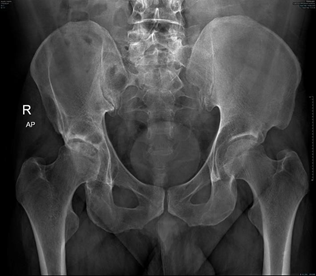

We did a retrospective case series with all patients underwent Total hip replacement surgery at Al-Moosa Specialist Hospital during 2022. Atotal of 15 patients with sickle cell disease underwent total hip replacement. Records of patient’s hematological and radio- graphical data were obtained. X-rays and MRI have been done preoperatively to all patients and were classified by Ficat& Arlet classification.

Harris Hip Score (HHS) was used for assessment of the functional outcomes. Follow up has been done to all patients after 6 weeks and then after 6 months to determine functional outcomes by clinical examination and by X-rays. Xrays were checked for any evidence of implant loosening, dislocation, or heterotopic ossification. Patients were seen by a hematology doctors and the study authors at every follow-up visits, and we documented medical and surgical complications. Failure was defined as the need for redo hip replacement surgery due to infection, dislocation, loosening, or surgical complications (Figure 5).